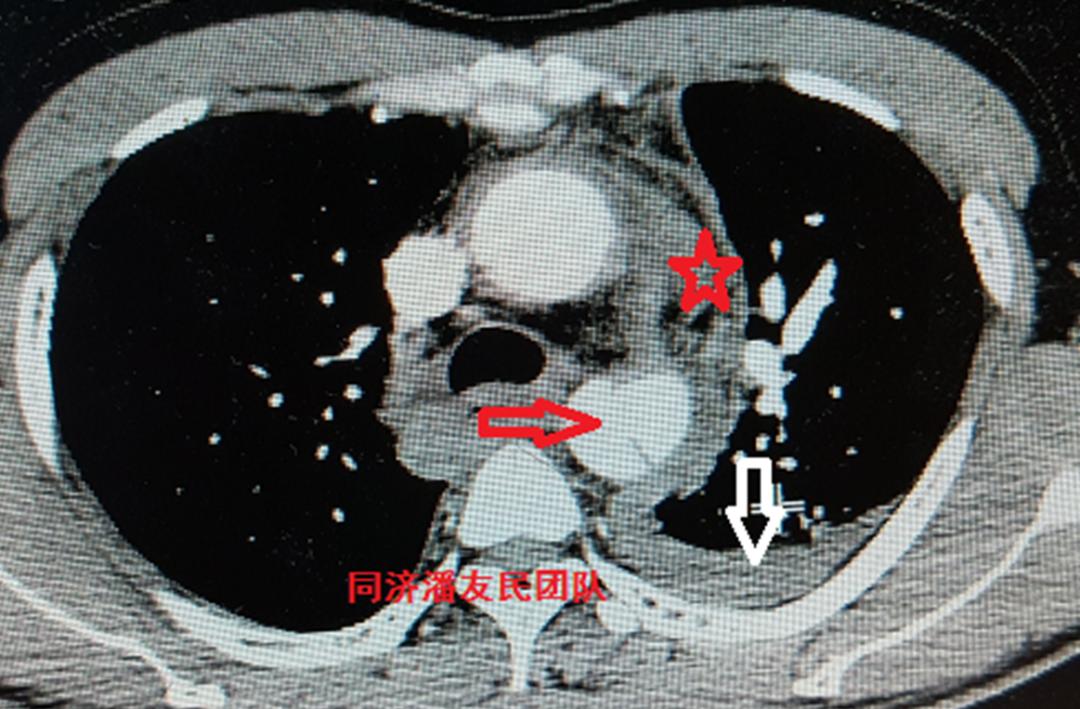

基层医院平扫CT提示胸降主动脉起始部内膜片影(图1),疑诊主动脉夹层(如何从平时CT发现主动脉夹层,请参考下文链接:没有CTA?这三招也能识别主动脉夹层!)。

入院后,胸腹主动脉CTA将主动脉及胸腹腔脏器一起进行全面评估。与图1平扫CT层面对应,图2显示降主动脉夹层。

红星号显示纵隔血肿,白箭头显示胸腔积液。